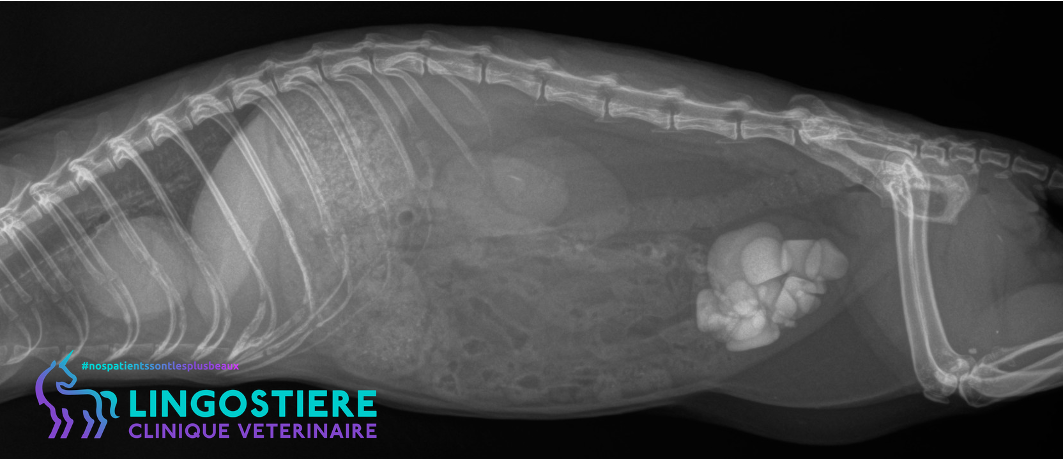

Cas clinique : strangurie et calculs

Découvrez la prise en charge d’Elphie : diagnostic radiographique, chirurgie de la vessie (cystine) et importance de l’alimentation adaptée.